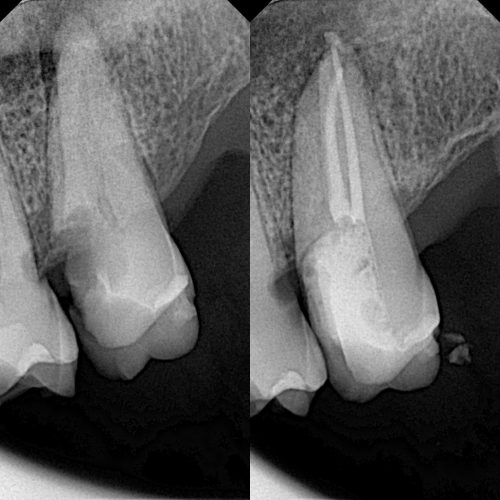

Endodoncia

En nuestra clínica, hemos adoptado una perspectiva avanzada al combinar la especialidad de endodoncia con la innovación de la odontología digital. Contamos con microscopio dental que nos permite brindarte un enfoque de tratamiento de alta precisión y comodidad sin precedentes.

IMG_7551 (1)